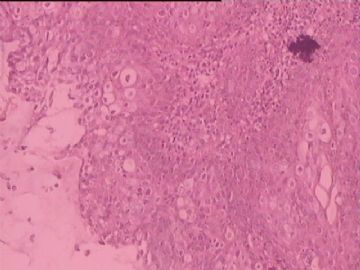

糜烂

图3